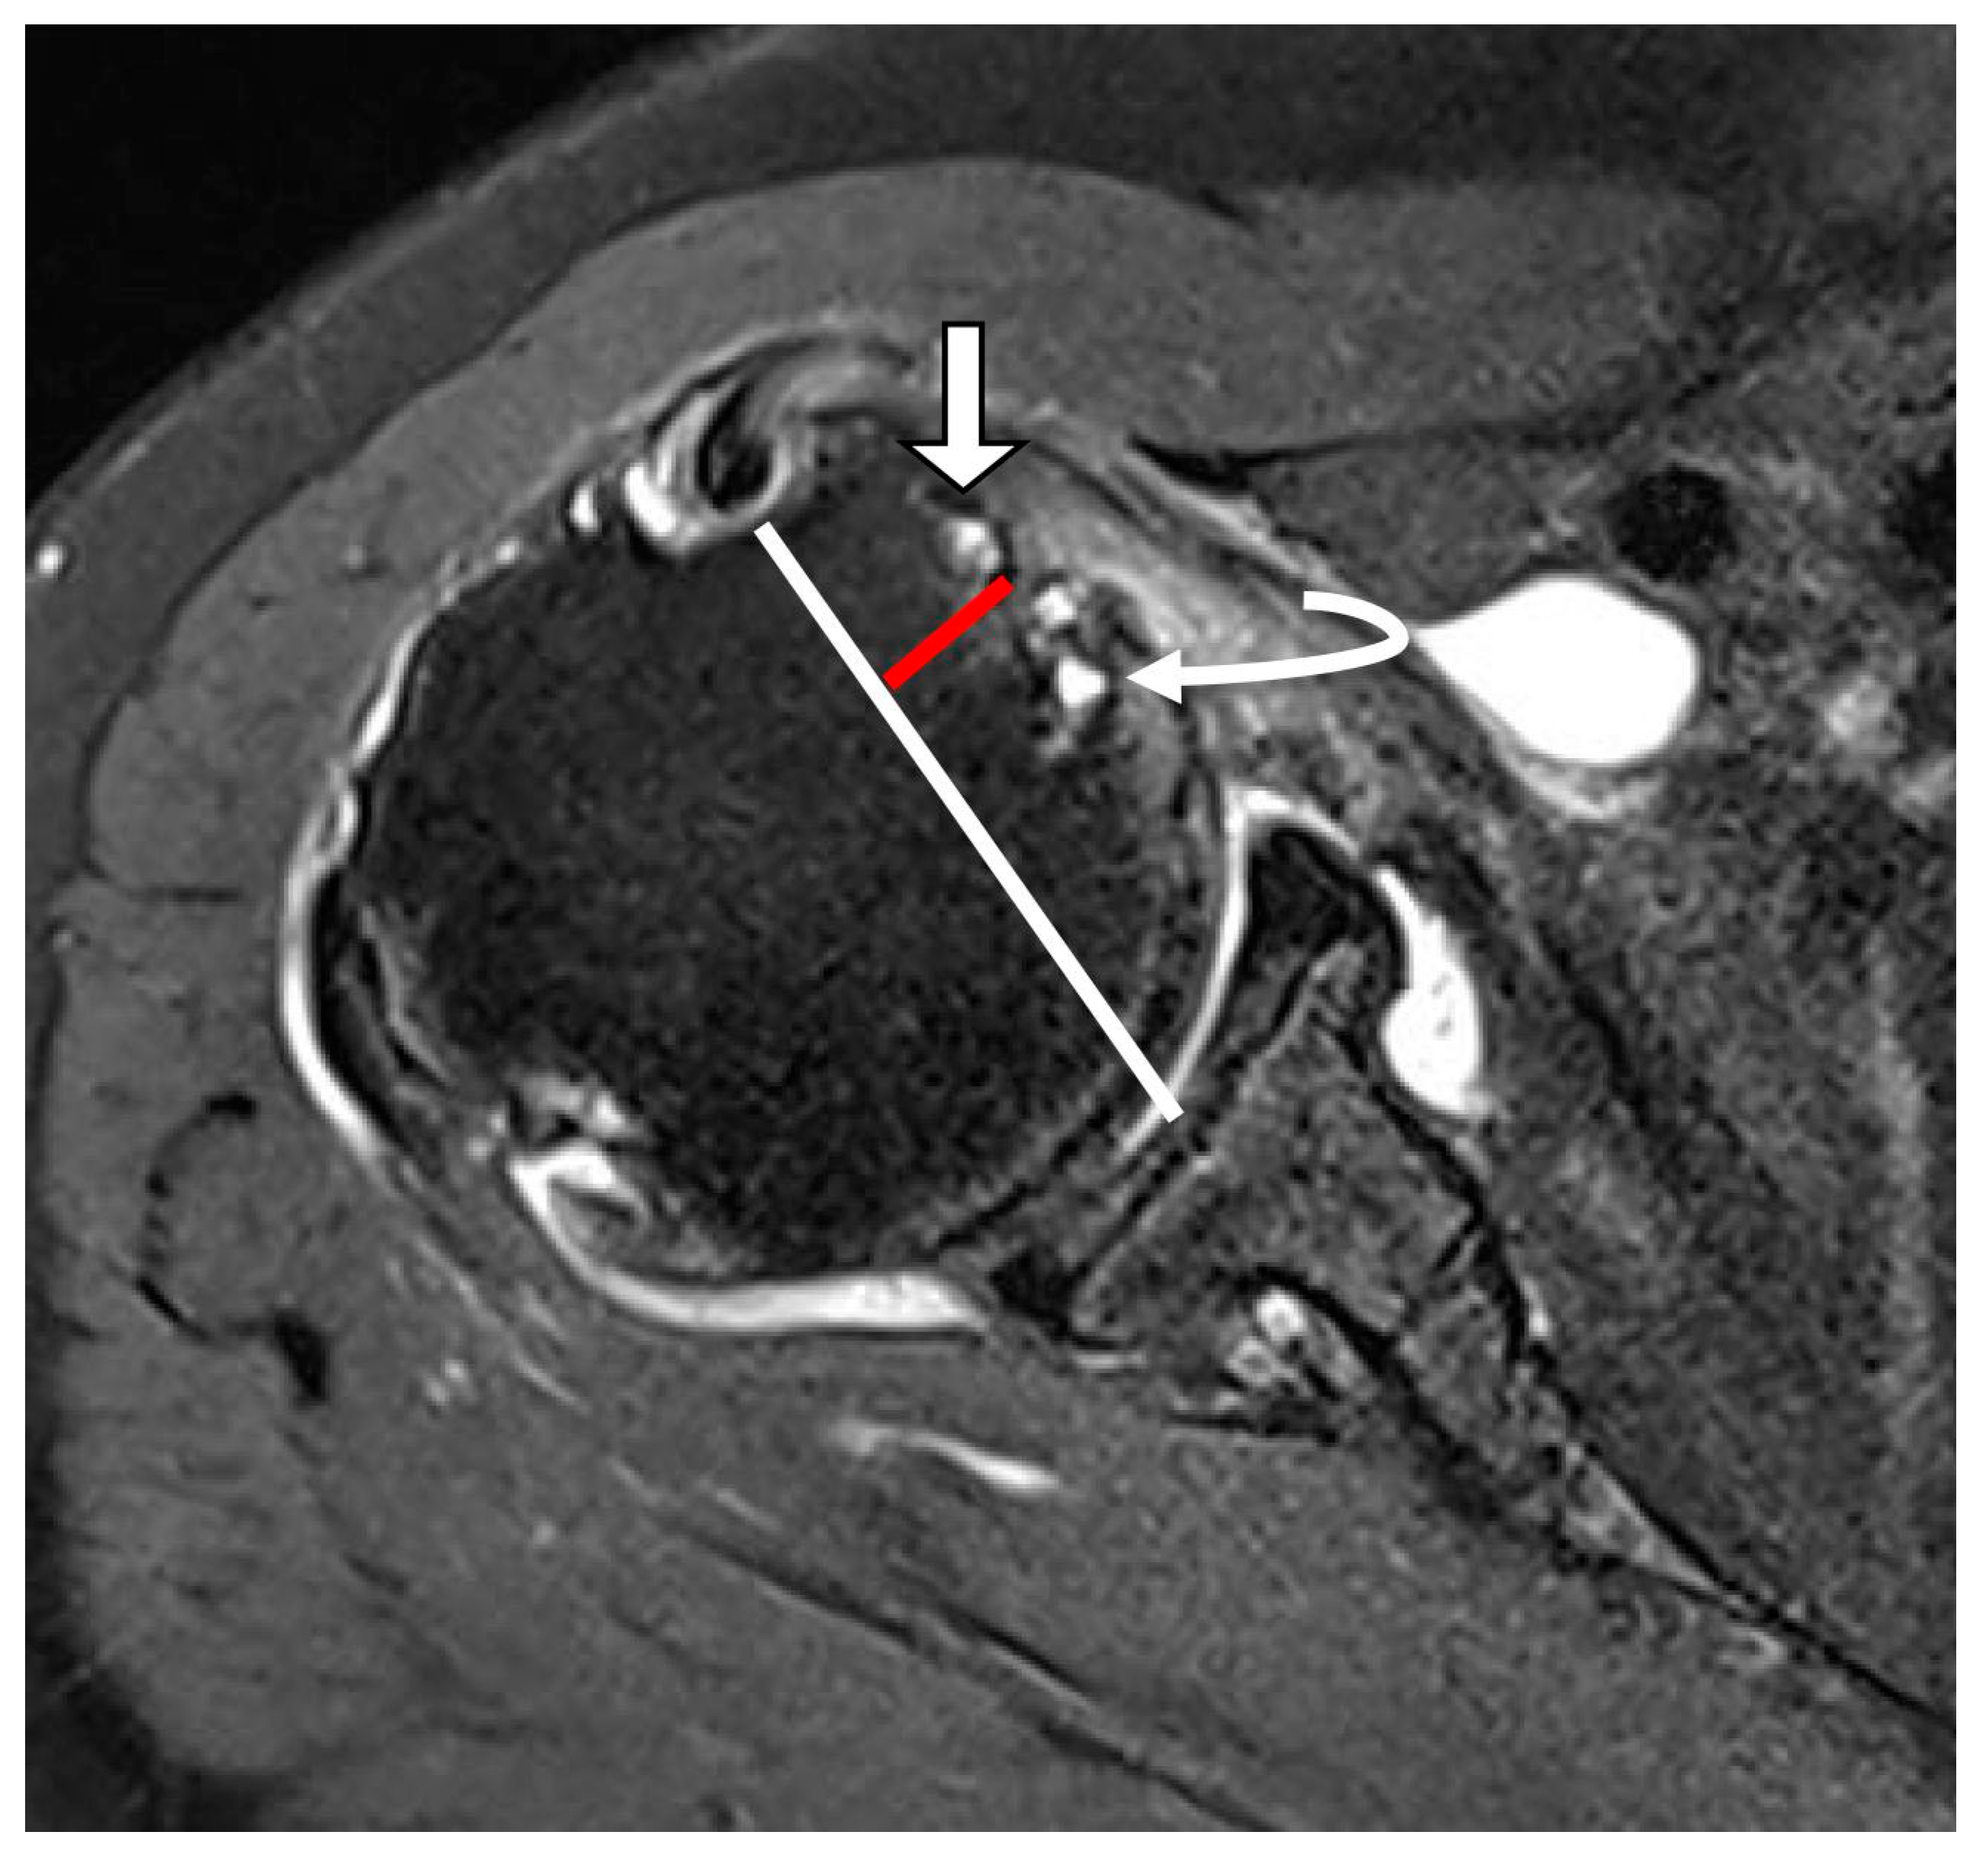

2.3. MRI Analysis

3.2. MRI Findings

| Subluxation or dislocation (%) | 13 (12.1%) | 22 (81.5%) | <0.001 | κ = 0.853 (p < 0.001) |

| LHBT subluxation | 31.815 | 10.267–98.593 | <0.001 | 22.836 | 3.993–130.605 | <0.001 |